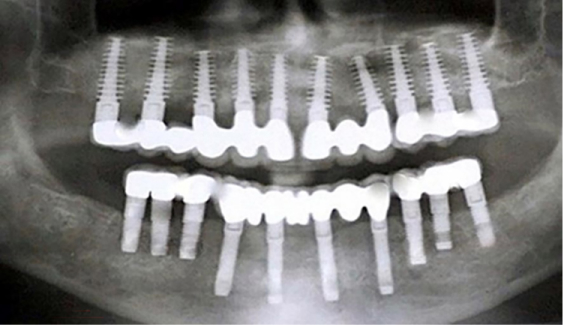

- Wider implants with poor-quality bone; longer implants whenever possible, with a min. of 8 mm length – 20mm.

- To obtain full-arch rehabilitation a min. of 6-8-10 implants are adequate, to achieve a predictable outcome.

- Computer-guided surgery minimizes errors in implant positioning.

- Implant position should be uniformly distributed along the alveolar arch and avoid distal cantilevers Implant Design